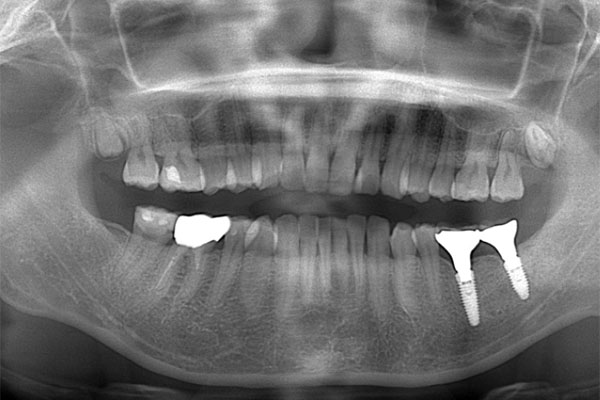

インプラント2本の予定ですので、インプラント同士をほぼ並行に埋入する計画を立てます。神経にインプラントが当たりますと、麻痺が起きたり出血の原因になりますので、

シュミレーション上でもしっかり神経とは距離をおきます。

【担当医師所見】

歯ぐきを切ってインプラントを埋入しました。埋入後は歯ぐきを縫って終わります。

この状態で4ヶ月待ちインプラントと骨の生着を待ちます。

左下奥歯は親知らずが原因でクラウン(かぶせ物)の下まで虫歯になっています。 またその手前の歯は根中央部に大きな透過像(黒い像)が見られます。クラウン除去後、マイクロスコープ下で確認したところ中央部は亀裂が入り保存不可能な状態になっており抜歯となりました。

また右上6番にも大きな透過像があり虫歯となっていることがわかります。

①親知らず手前の歯はクラウン(白い不透過像)直下に大きな透過像(黒い部分)が見られこのような場合は抜歯になる確率が高いです。

②歯根分岐部(中央部)に及ぶ歯周炎ー根尖性歯周炎の原因はクラウン除去後にマイクロスコープ下にて破折線を確認したため抜歯となりました。